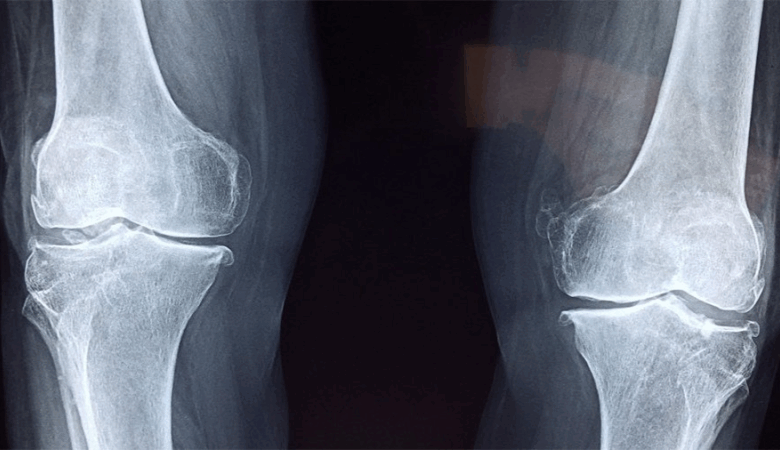

استراتيجية وطنية جديدة للتقصّي والتكفّل بمرض هشاشة العظام

في إطار تعزيز الجهود الوطنية لمكافحة الأمراض الصامتة، استقبل وزير الصحّة، مصطفى الفرجاني، امس الأربعاء 10 سبتمبر 2025، وفداً عن الجمعيّة التونسية لمقاومة داء المفاصل، حيث تمّ تقديم مشروع الاستراتيجية الوطنية للتقصّي والتكفّل بمرض هشاشة العظام.

وتشمل هذه الإجراءات: الكشف المبكر والمتابعة الدورية للمرضى، وإحداث مراكز متابعة الكسور للوقاية الثانوية، وضمان النفاذ العادل إلى الأدوية والعلاجات، إضافة إلى إرساء سجل وطني للكسور يسهّل التخطيط الصحي، فضلاً عن دعم البحث العلمي والتكوين والتوعية.

وشدّد وزير الصحّة، في ختام اللقاء، على ضرورة اعتبار هشاشة العظام أولوية وطنية، مؤكداً أنّ التشخيص المبكر والتكفّل الشامل يجب أن يشمل كافة الجهات في إطار مقاربة عادلة ومنصفة.